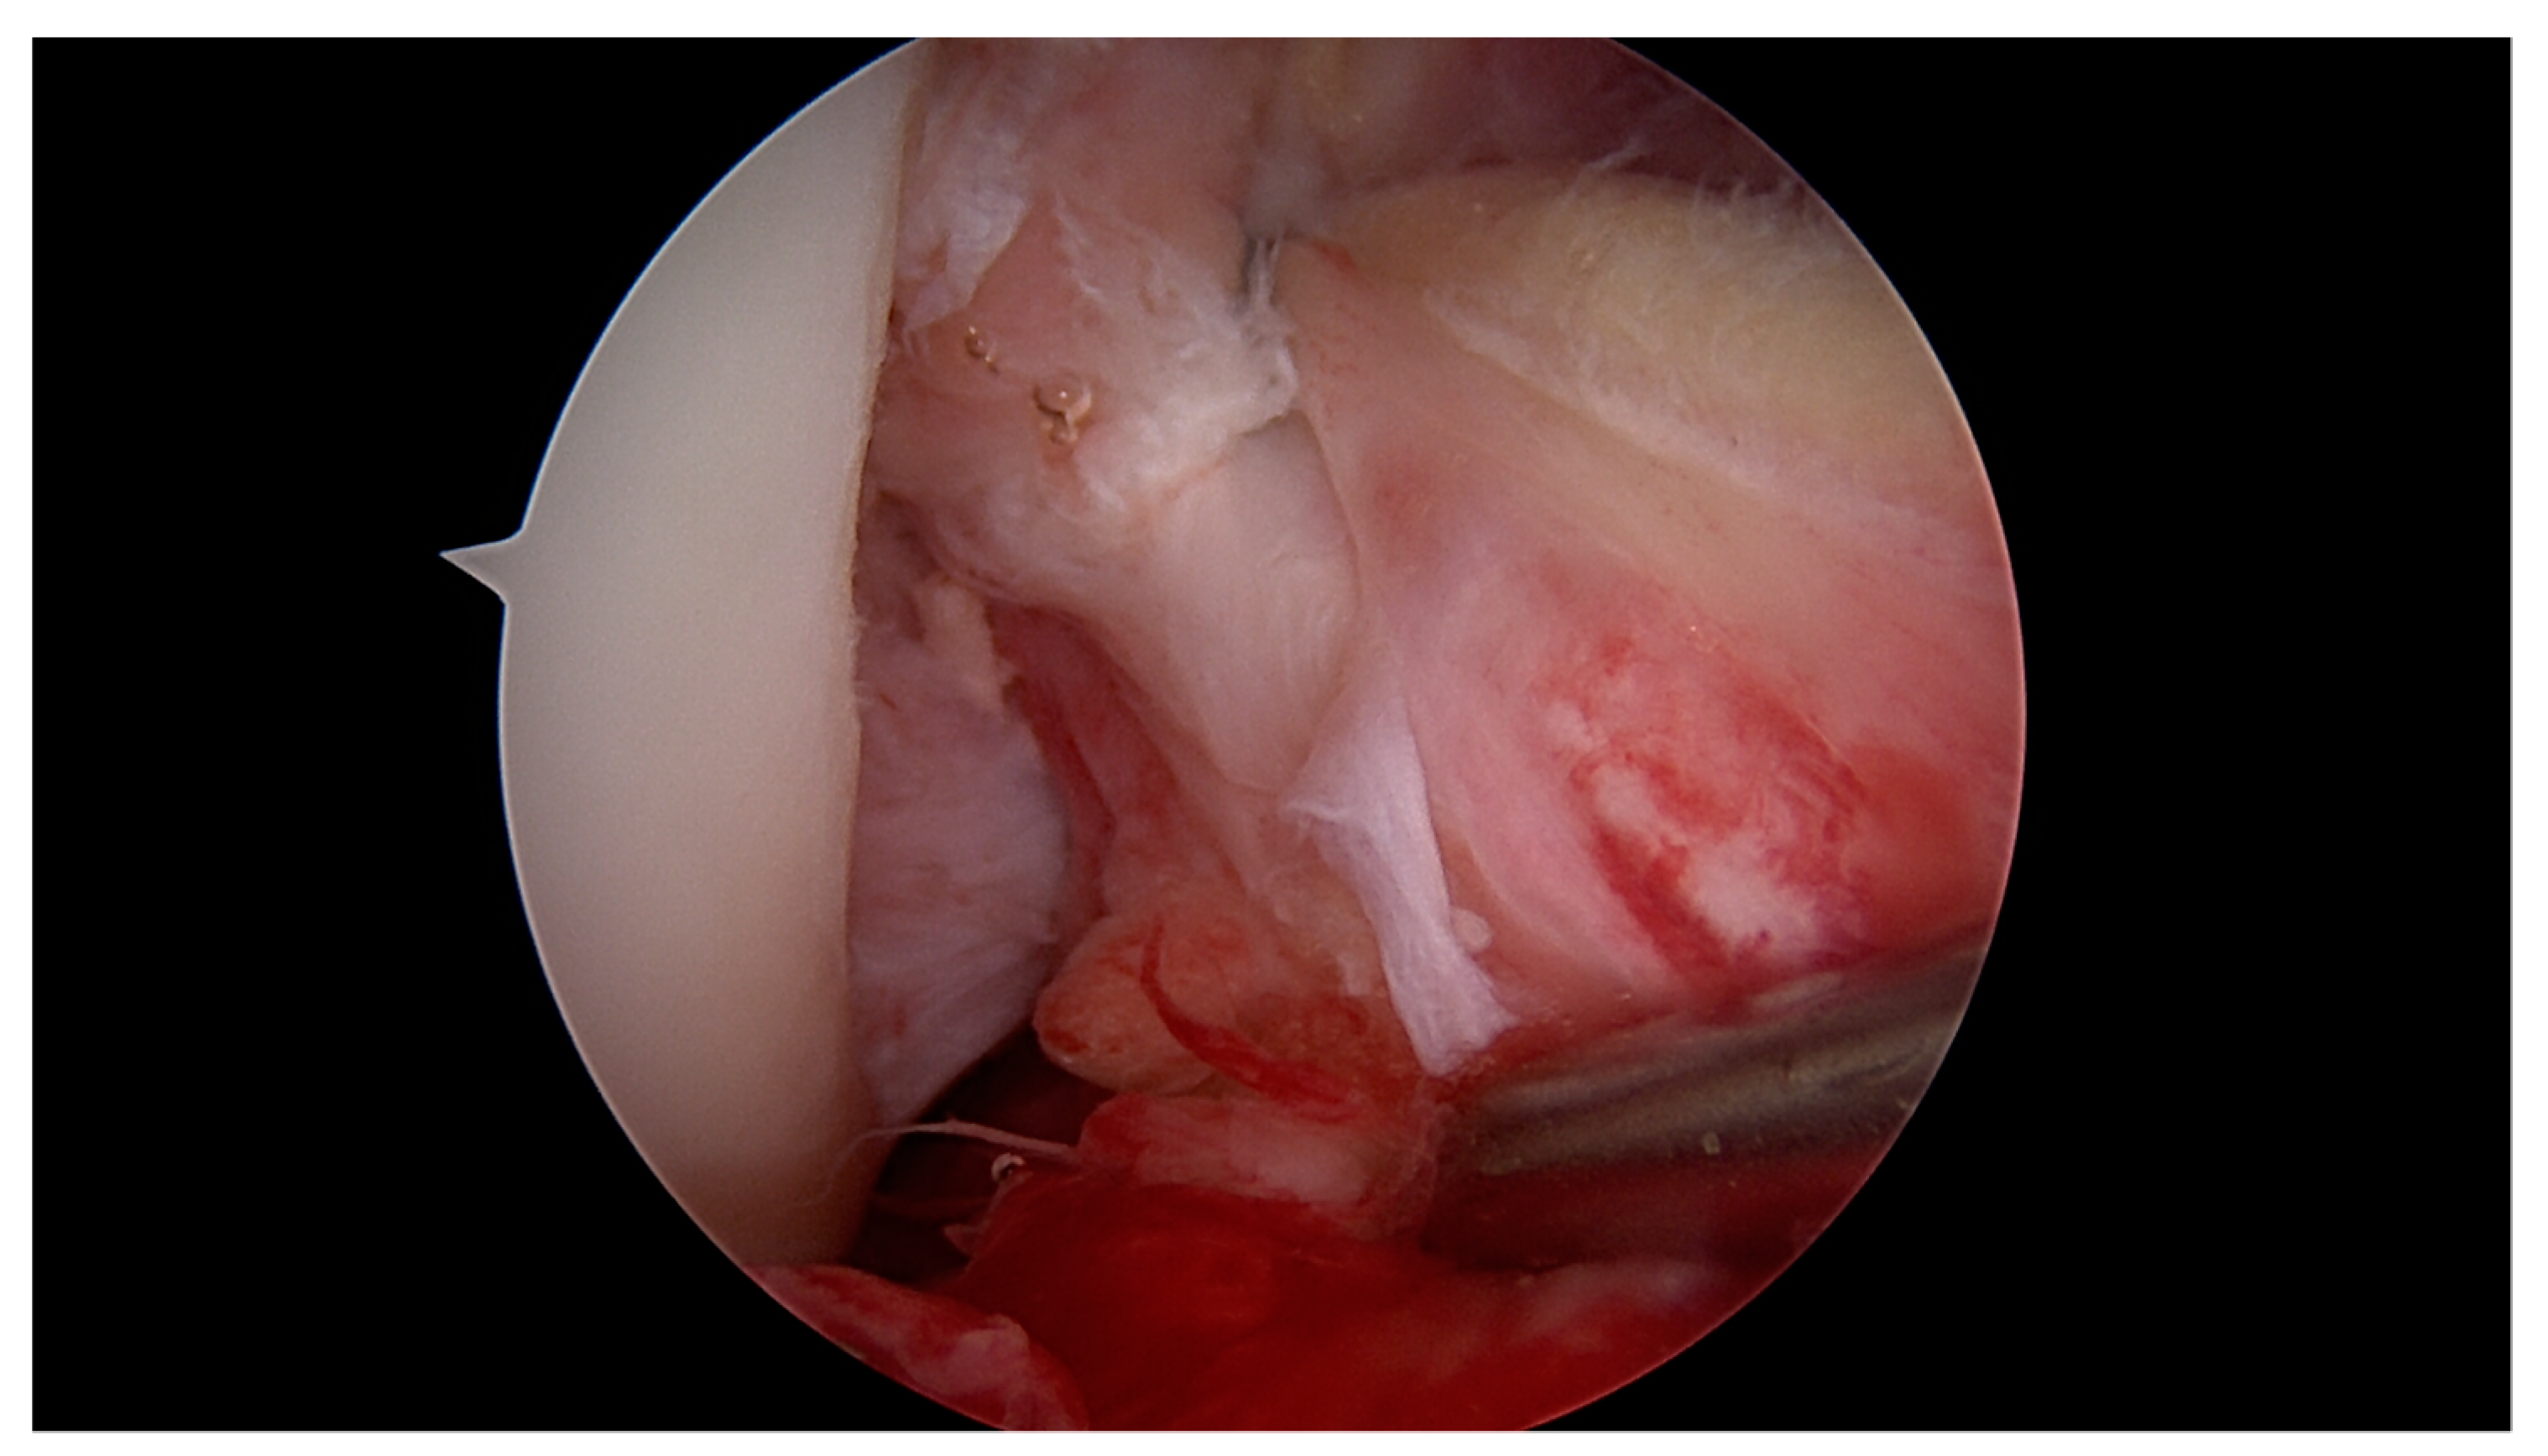

2.1. Surgical Technique and Rehabilitation